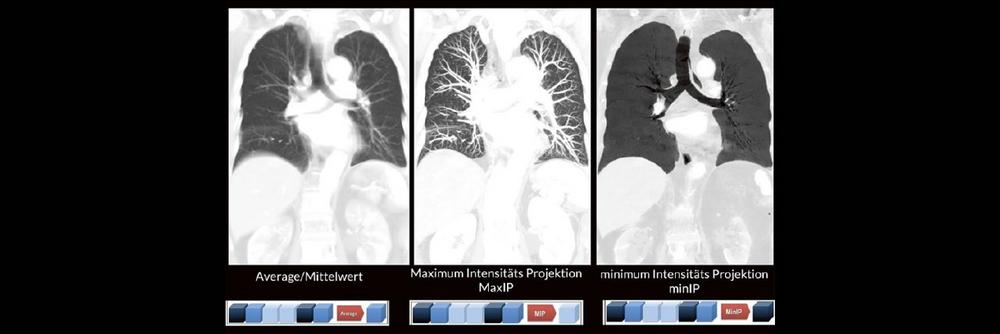

Alex Riemer Moderne CT-Scanner unterstützen die Anwenderinnen und Anwender bei der Durchführung der meisten CT-Untersuchungen. Hierzu zählt auch das automatische Erstellen von streng coronalen und sagittalen Multiplanaren Reformatierungen (MPR´s). Es gibt jedoch CT-Untersuchungen, bei denen die MPR´s individuell an die Anatomie angepasst werden müssen. Doch gerade bei diesen Bildnachverarbeitungen gibt es oft Unsicherheiten darüber, worauf